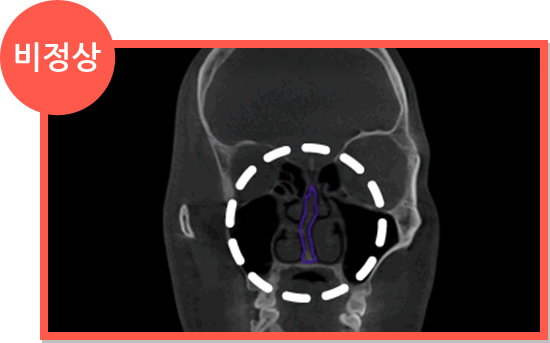

비염 CT 정상 소견 비염 CT 비정상 소견